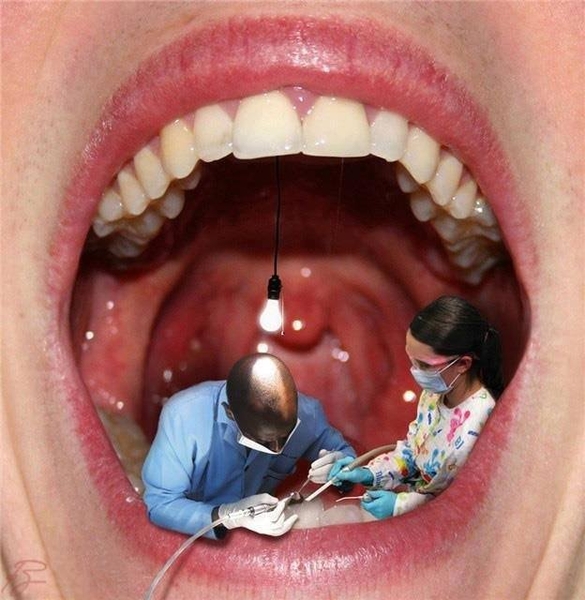

Điều trị nội nha

Mỗi năm trên thế giới hàng triêu chiếc răng đã được cứu sống nhờ điều trị nôi nha....